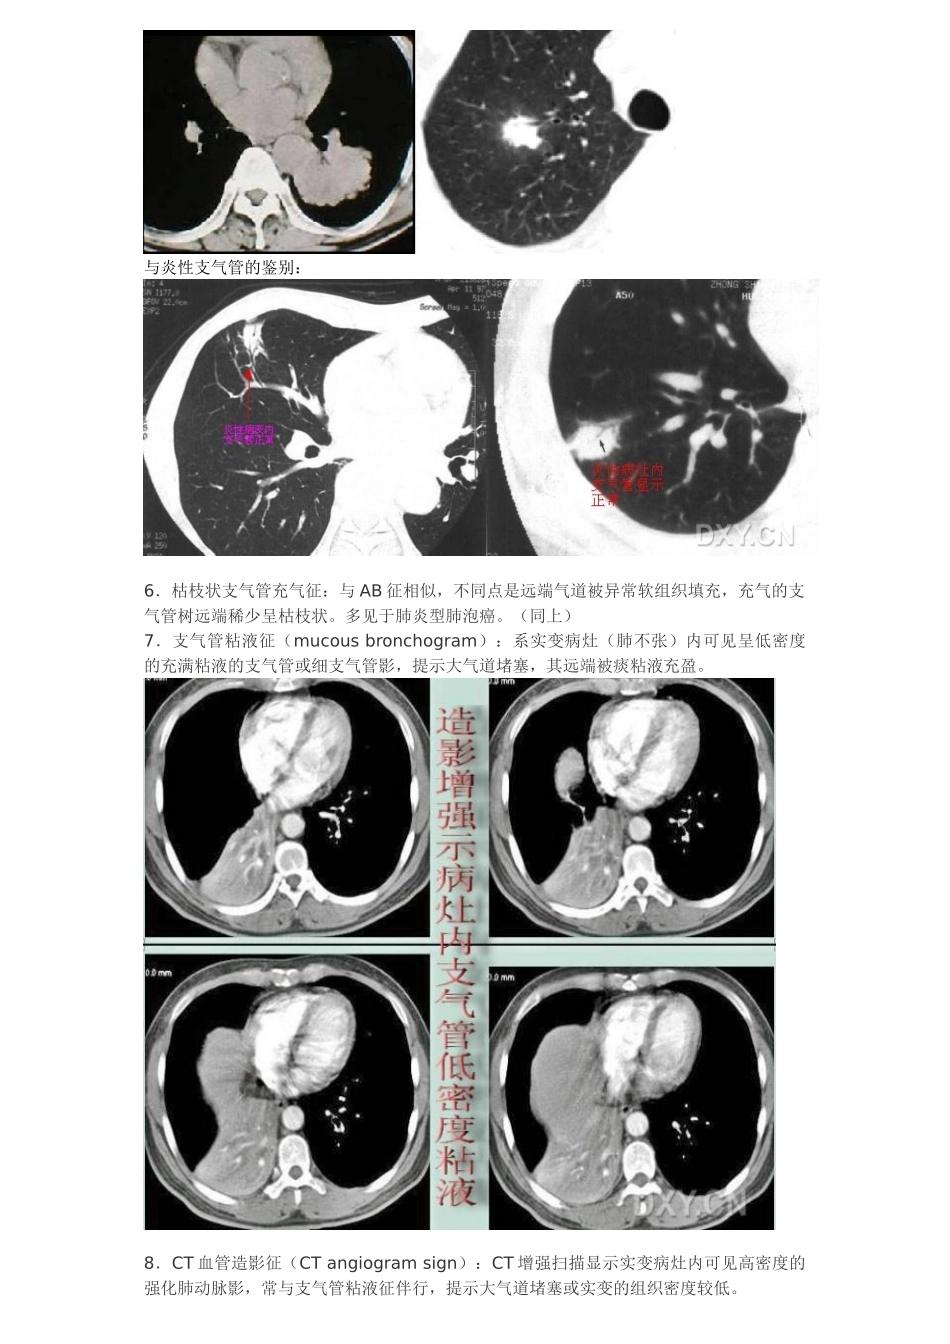

常见胸部 CT 征象1.树芽征(tree-in-bud sign):即小叶核心分布的结节,源于小气道本身的疾病,HRCT 表现为与支气管血管束或小叶核心相连的、直径 3~5mm 大小的结节影、短线状影或分叉状结构。2.印戒征(signet-ring sign):系支气管扩张的典型征象,较大的环状含气影(印戒的指环)为扩张增厚的支气管,其相邻小的软组织影(指环上镶崁的宝石)为伴行的肺动脉影。3.铺路石征(Crazy-paving appearance):系磨玻璃影的背景下同时伴有网格状或细网格状小叶间隔和小叶内间隔增厚。4.界面征(interface sign):血管或支气管等肺实质结构的边缘或肺的胸膜面出现不规则的界面,提示间质增厚。5.支气管充气征(air bronchogram,AB 征):系实变病灶内可见正常充气的支气管或细支气管影,提示气道通畅,而病变位于肺泡。支气管征(小管征、空气支气管征、枯/树枝征、细支气管充气征、病理性支气管像、阳性支气管征、支气管充气征、支气管气像、支气管管征、支气管截断征):是由瘤组织在细支气管与肺泡表面呈伏壁式生长而不充盈管腔,管腔通畅。表现为长、短不一的管状分支状低密度影。可以呈细条状(直径≤1mm)的空气密度影,见于连续数个相邻的层面上,病理上也可以为扩张的细支气管。其发生率也较高,约占 33.3%.在影像上表现可以多种多样,因此名称也较多。支气管征可见于肺癌,肺炎性病变或淋巴瘤。但以肺癌较多见,常与空泡征同时存在,与一般急性炎症空气支气管造影征相鉴别。枯/树枝征细支气管充气征与炎性支气管的鉴别:6.枯枝状支气管充气征:与 AB 征相似,不同点是远端气道被异常软组织填充,充气的支气管树远端稀少呈枯枝状。多见于肺炎型肺泡癌。(同上)7.支气管粘液征(mucous bronchogram):系实变病灶(肺不张)内可见呈低密度的充满粘液的支气管或细支气管影,提示大气道堵塞,其远端被痰粘液充盈。8.CT 血管造影征(CT angiogram sign):CT 增强扫描显示实变病灶内可见高密度的强化肺动脉影,常与支气管粘液征伴行,提示大气道堵塞或实变的组织密度较低。被用来描述大叶型细支气管肺泡癌(腺癌)。是肿瘤沿肺泡壁生长侵润尚未完全破坏肺泡间隔,但使肺泡壁增厚或邻近肺泡内有分泌物,部分肺泡内仍有含气,形成肺炎型改变,增强时可见在病变中穿行的血流强化,称 CT 血管造影征,多见于肺泡癌。当肺血管进入结节或终止结节时,血管常狭窄、堵塞、截断等。文献认为其中以肺静脉包被(肺静脉包被征)...